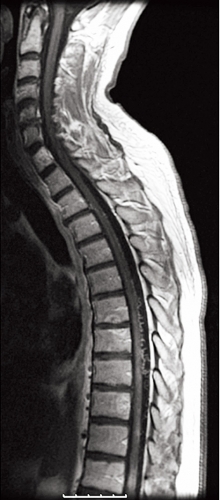

På akutmottagningen tolkades patientens besvär som neuropati, och han behandlades med injektion tiamin (Betabion). Eftersom patienten försämrades ytterligare, genomfördes samma dag akut MRT av hela ryggen, vilken visade ett uttalat ryggmärgsödem från bröstrygg till conus medullaris. Dorsalt om ryggmärgen sågs vidgade blodkärl, varför man misstänkte att det rörde sig om en spinal dural arteriovenös fistel (Figur 1). Neurokirurgisk klinik kontaktades för övertagning.

Diagnostik. Den kliniska bilden och spinal MRT är helt avgörande för diagnosen. Okunnighet hos kliniker eller radiolog kan få som konsekvens att diagnosen ställs för sent eller inte alls, medan patienten utvecklar en obotlig parapares. De typiska fynden vid MRT är ödem och lätt svullnad av ryggmärgen torakolumbalt samt vidgade blodkärl (vener) dorsalt perimedullärt. Ödemet uppvisar hög signal centralt i ryggmärgen på T2-viktade bilder. De vida perimedullära venerna syns i cerebrospinalvätskan som slingriga strukturer med låg signal på T2-viktade bilder och hög signal på T1-viktade bilder efter intravenös kontrastmedelstillförsel.